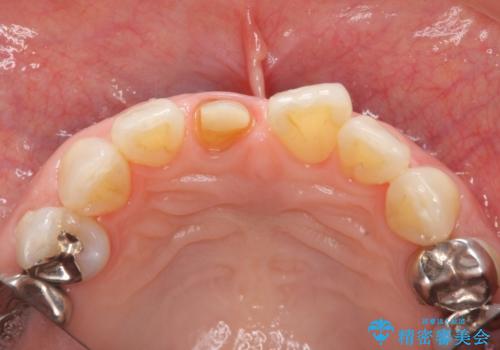

前歯の変色 セラミック審美補綴

- 前歯の変色の改善を希望され来院されました.

以前に神経が死に、根管治療を行った歯の変色が認められたためセラミックによる審美補綴治療を計画します。

神経の死んでいる歯について

神経治療を行い補綴(かぶせもの)治療を行わないと、変色が目立ち審美障害を起こすことがあります。

このような場合、セラミックによる審美改善が治療の一案として提案されます。